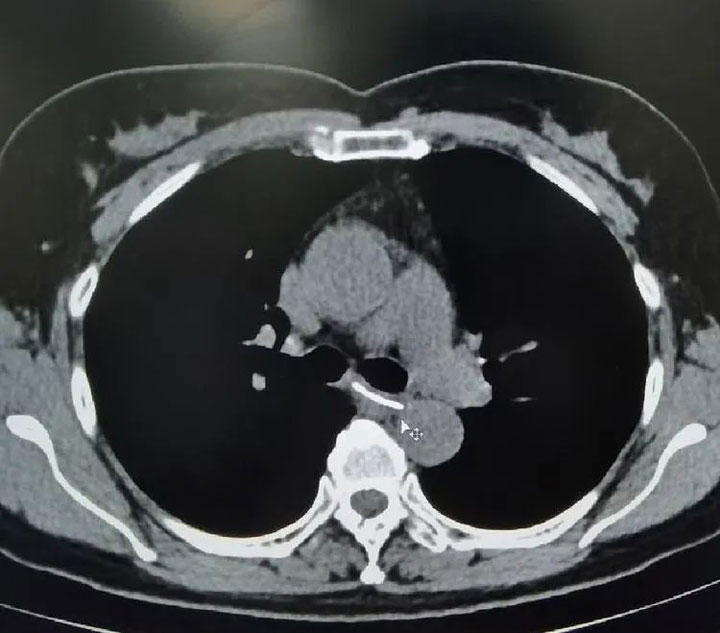

▲影像检查可见食管异物

三个小时后,她走进了广济医院消化内科诊室。“早晨吃过饭,觉得恶心、想吐,胸口堵得慌,好像什么卡住了。我就使劲喝水,结果现在不仅堵,还疼起来了。”结合钱女士的主诉,接诊医生为其查体行CT检查后,发现其食管中段异物。